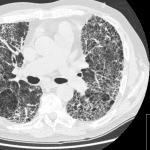

Interstitial Lung Disease and Pulmonary Fibrosis

Introduction Interstitial lung diseases (ILDs) affect the lung interstitium, i.e. the space between the alveolar epithelium and the capillary endothelium, causing inflammation and fibrosis. The two main types of interstitial…